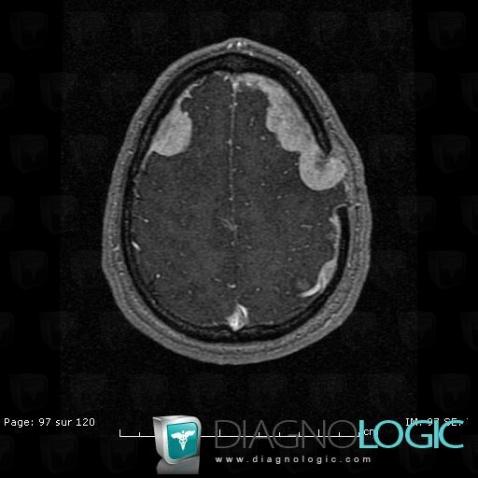

Langerhans cell histiocytosis, Supratentorial peri cerebral spaces, MRI

Here is the specific information in the key image above:

- Diagnosis Langerhans cell histiocytosis, Location(s) Supratentorial peri cerebral spaces, with gamuts Diffuse meningeal enhancement